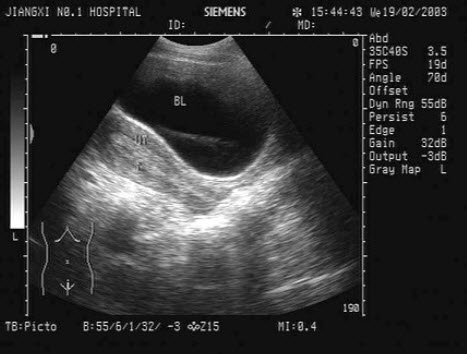

29、单项选择题

甲状腺肿大常见于下列哪些疾病及声像图表现()